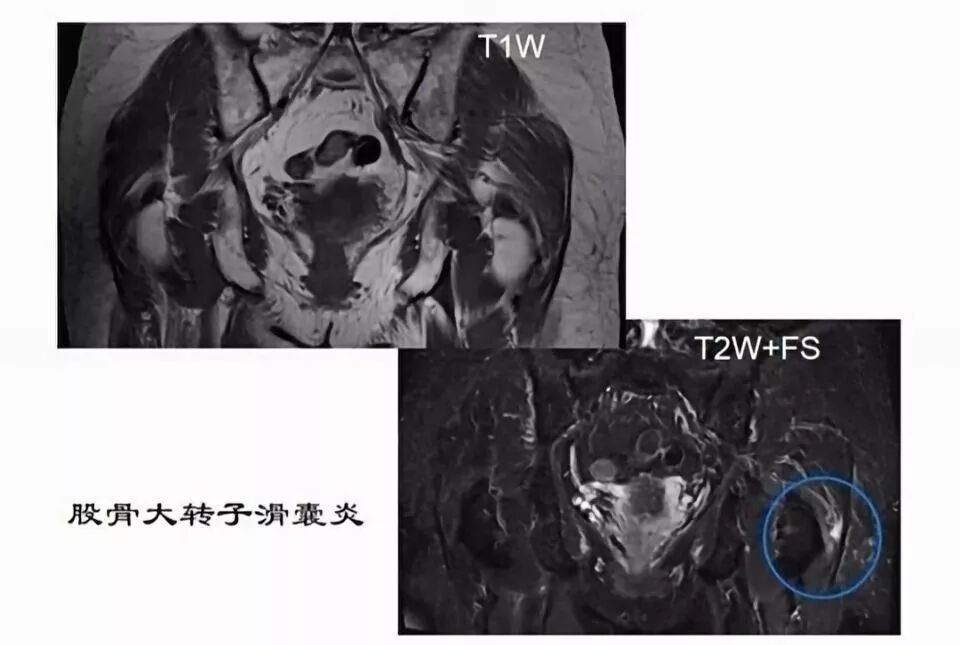

滑囊是关节囊外的囊性结构,可与关节囊相通,其作用是减少肌腱、骨和皮肤之间的摩擦。可以分为先天性滑囊和获得性滑囊。